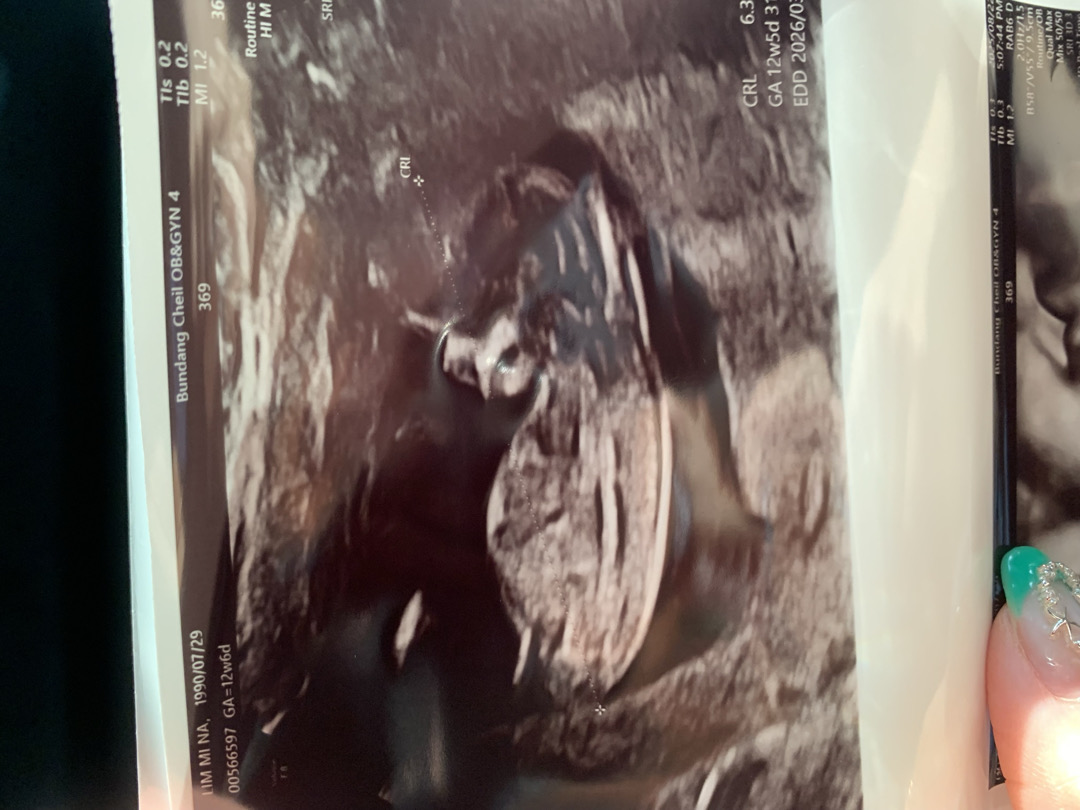

각도법 보는방법 어캐 알아요..??

오늘 1차 정밀초음파 했는데 혹시 각도법 아시는분 계신가여???ㅠㅠ 봐도 모르겠네요…ㅠㅠ

아들같아요

저는 아들에,,, 조심히 한표요!!